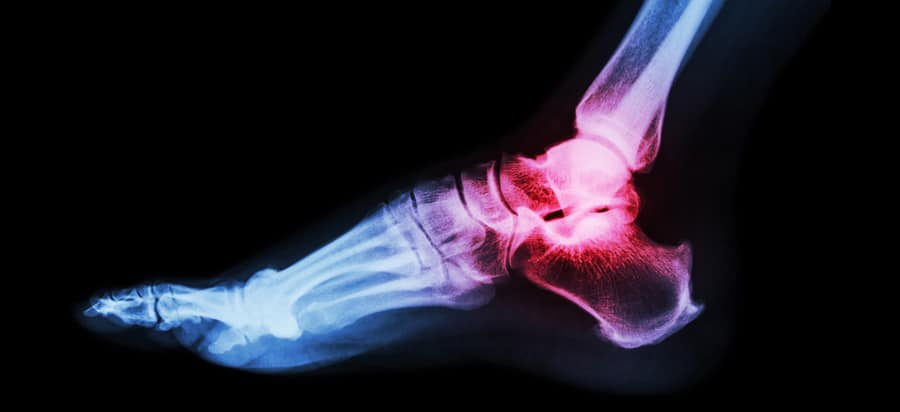

X-ray

As the most commonly used imaging technique, X-rays can diagnose most ankle fractures. They will also determine the severity of the ankle fracture and if you have other fractures in your leg or foot.